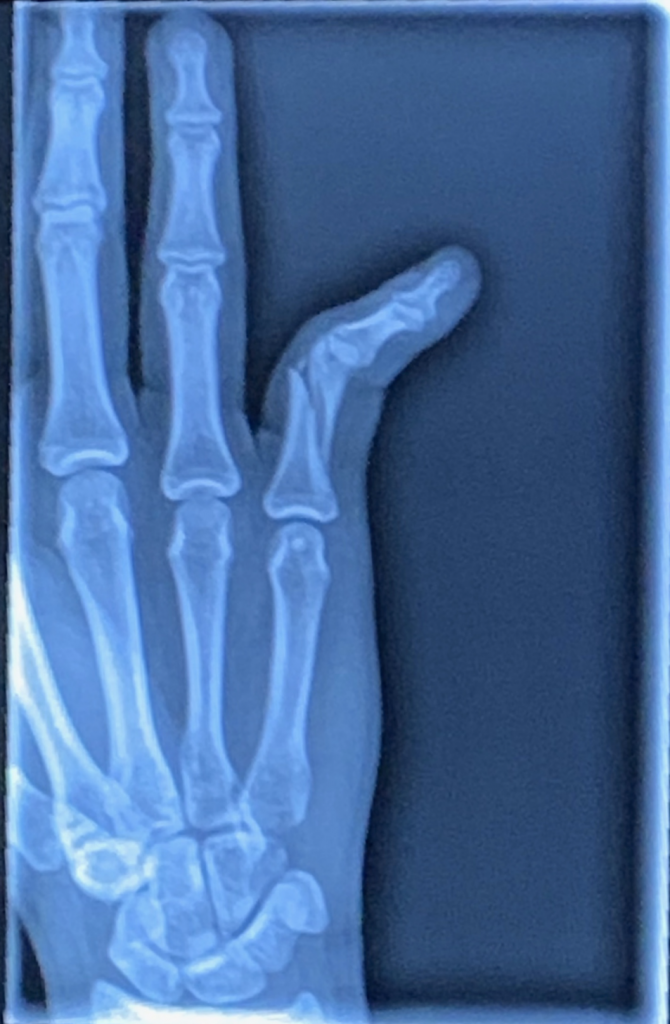

After the final point of my volleyball game, my friend asked me what was wrong with my hand and I quickly realized that one of my fingers was very bent, to say the least. I did not think much of it and simply thought I would be back to playing volleyball within a week or two.

To my dismay, I had a spiral fracture in my right small finger which meant no volleyball, surgery, and months of rehabilitation. After my injury, I got an appointment within 24 hours and was scheduled for surgery within a week. My experience at HSS was truly remarkable. Injuring my dominant hand during finals week was less than ideal, however Dr. Trehan always wrote notes to my teachers and gave me lots of advice! He also answered all my mom’s phone calls and the many questions that she had! I was taken care of so well and every person I spoke to made me their top priority. Thanks to Dr. Trehan, I now have a fully functioning hand!